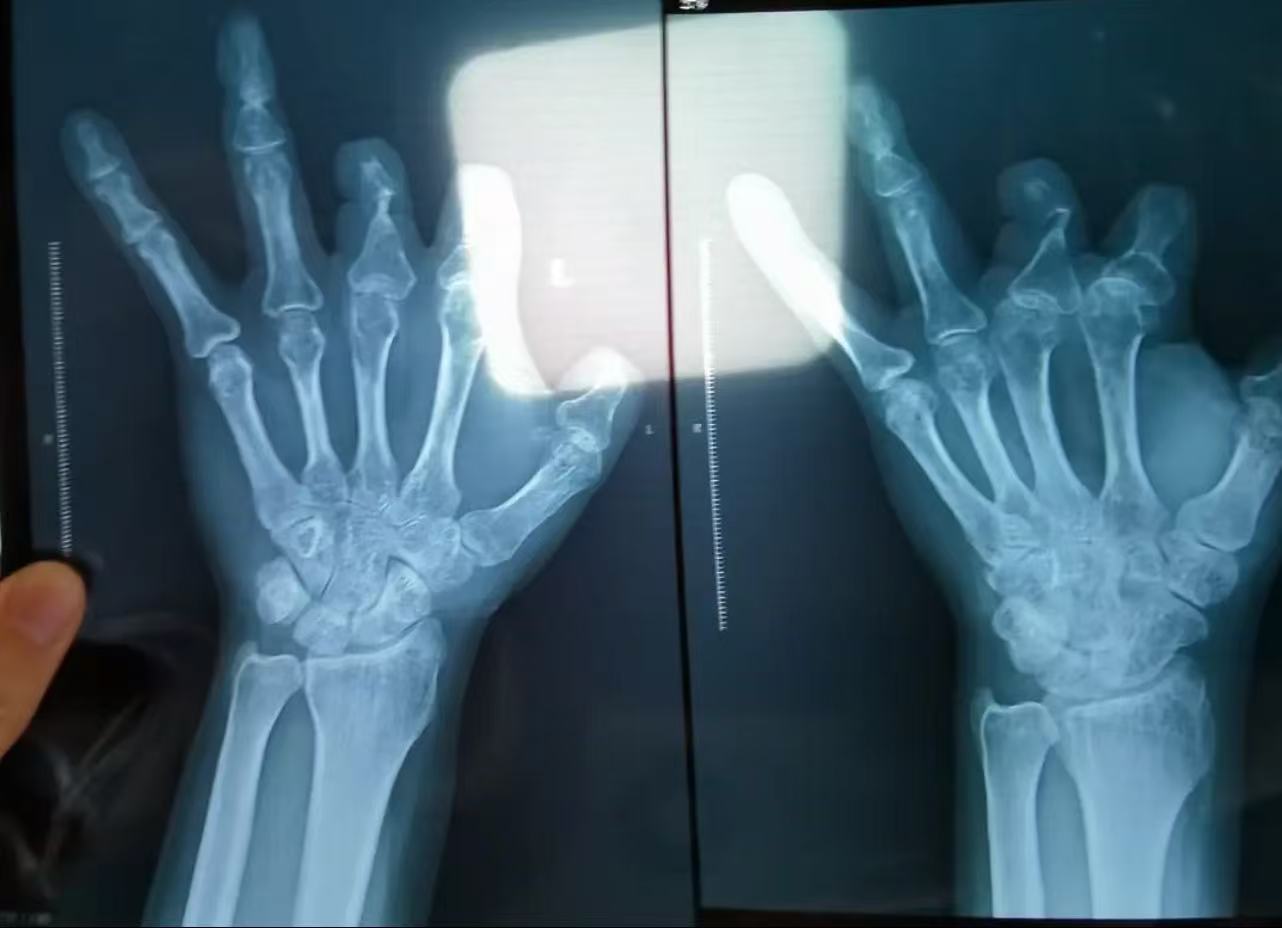

可术后恢复极差,手指还是坏死了。彭先生心生疑虑,在律师建议下拍了X光片——结果令人毛骨悚然:那6个本该留在体内的吻合器,一个都没影儿!

要知道,这种装置含有不锈钢针,X光下清晰可见,绝不可能“被吸收”或“消失”。唯一的解释是:压根没放进身体里。

2018年,木工王海森在工地被电锯削掉拇指,也被送到郑大一附院。手术后欠费3万,其中2个吻合器就花了3.36万。一年后,有人悄悄告诉他:“那玩意儿根本没用。”他不信,直到2021年拍X光片——果然,空空如也。